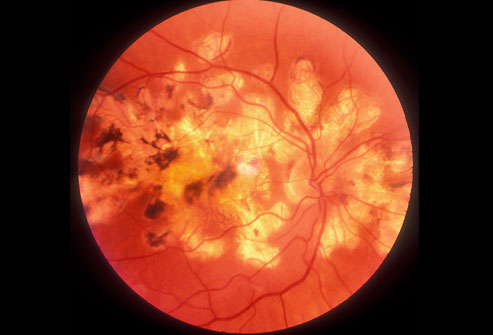

三分之一的糖尿病患者甚至不知道自己患了糖尿病。糖尿病会引起心脏病、中风、肾病、因视网膜血管受损导致失明(如图所示)和其他严重问题。你能够通过饮食、运动、减肥、和药物治疗来控制糖尿病,特别是在你发现得及时的情况下。2型糖尿病是常见的疾病。1型糖尿病的患者通常是儿童和年轻人。